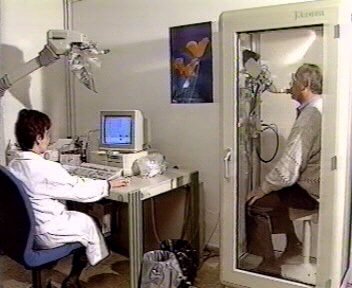

RADIOLOGIA (1) |

RADIOLOGIA (2) |

| RADIOLOGIA |